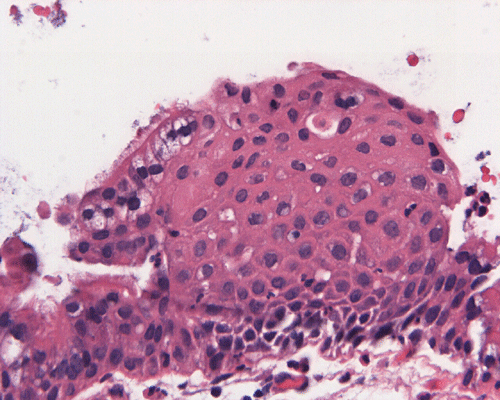

Clinical informationThe patient was a 45 year-old man who presented with staring episode that is reminiscent of a seizure. MRI examination disclosed a cystic sellar mass that deflected his optic nerve. There was no clear visual loss.

What is your diagnosis? Discussion